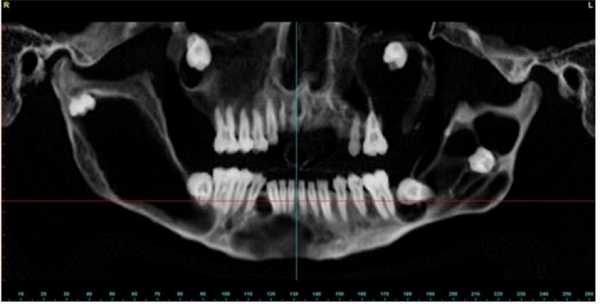

Пациент муж., 17 лет. КТ-исследование подтверждает наличие новообразований (Рис. 6,7).

Рис. 6. Ортопантомограмма пациента с одонтогенными кератокистами.

КТ свидетельствует о наличии множественных одонтогенных кератокист. Определяются множественные овальные, зубосодержащие полости, с четкими ровными справа и полицикличными контурами слева, однородной рентгенпрозрачности. В теле и ветвях нижней челюсти образование распространяется вдоль кости от премоляров справа и моляров слева и до вершин мыщелковых отростков. Костные структуры незначительно увеличены в размерах за счет вздутия, кортикальные пластины истончены. Дивергенция корней зубов № 43, 44. Объемные зубосодержащие образования верхней челюсти вросли в верхнечелюстные синусы, занимая практически весь объем, а справа — распространилось в подвисочную ямку.

Рис. 7. КТ исследование свидетельствует о наличии множественных одонтогенных кератокист.